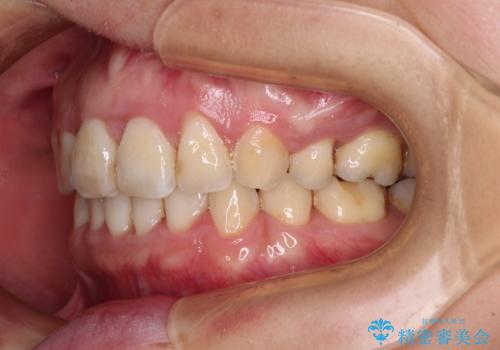

- 出っ歯と口の閉じにくさ、デコボコを気にして来院された患者様です。

口元の突出感を改善するため、上下左右第一小臼歯4本の抜歯を行い、ワイヤー装置による矯正治療を行うこととしました。